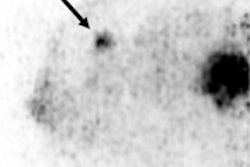

3D reconstructions of Mammi PEM breast images acquired in March (top) and April (bottom) during neoadjuvant chemotherapy show sharp reduction in tumor volume, from 0.8445 cm3 to 0.1705 cm3.Although whole-body PET has proved to be valuable at multiple stages in breast cancer assessment, investigators have reported a reduced ability of whole-body PET to detect small, well-differentiated in situ breast carcinomas smaller than 1 cm, according to the company.